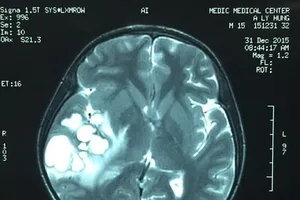

Nghi u não, mổ ra là ổ ấu trùng sán dải heo